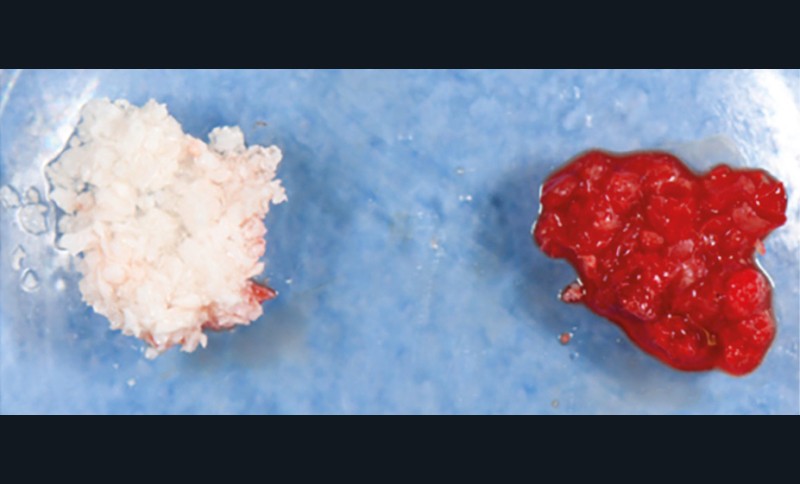

Actes préopératoires

La couronne a été déposée et une vis de couverture mise en place. La patiente a reçu un nettoyage supra-gingival général avec une attention particulière pour l’implant 47, et une irrigation locale avec du gel de chlorhexidine et du peroxyde d’hydrogène pour réduire l’inflammation des tissus. De l’amoxicilline (3 x 500 mg) a été prescrite, à commencer la veille de l’intervention chirurgicale.